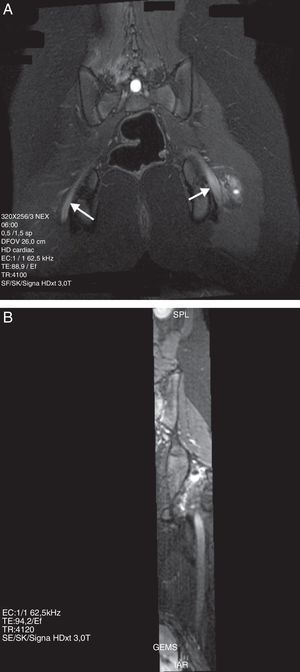

La lipomatosis del nervio ciático, también conocida como hamartoma fibromatoso, es una condición seudotumoral rara caracterizada por el engrosamiento fusiforme de un nervio por hipertrofia anómala del tejido fibroadiposo. La apariencia de esta entidad en la RM es patognomónica. En las secuencias ponderadas en T1 muestra el patrón fascicular del nervio, hipointenso, surcado por tejido hiperintenso similar a la señal de la grasa que se distribuye uniformemente entre las fibras del nervio. En las secuencias ponderadas en T2, y en particular en aquellas con saturación grasa o STIR (short tau inversión recovery), el nervio aparece homogéneamente hipointenso debido a la supresión del componente graso y a la baja señal del patrón fascicular normal. La cantidad de componente graso es variable43,44 (fig. 7).

Paciente de 73 años que presentaba parestesias leves en el territorio peroneo de ambos lados. En las imágenes ponderadas T1 se observa aumento de grosor del nervio ciático de ambos lados a expensas de una hipertrofia del componente graso intraneural, hallazgo compatible con lipomatosis bilateral del nervio ciático (flecha).